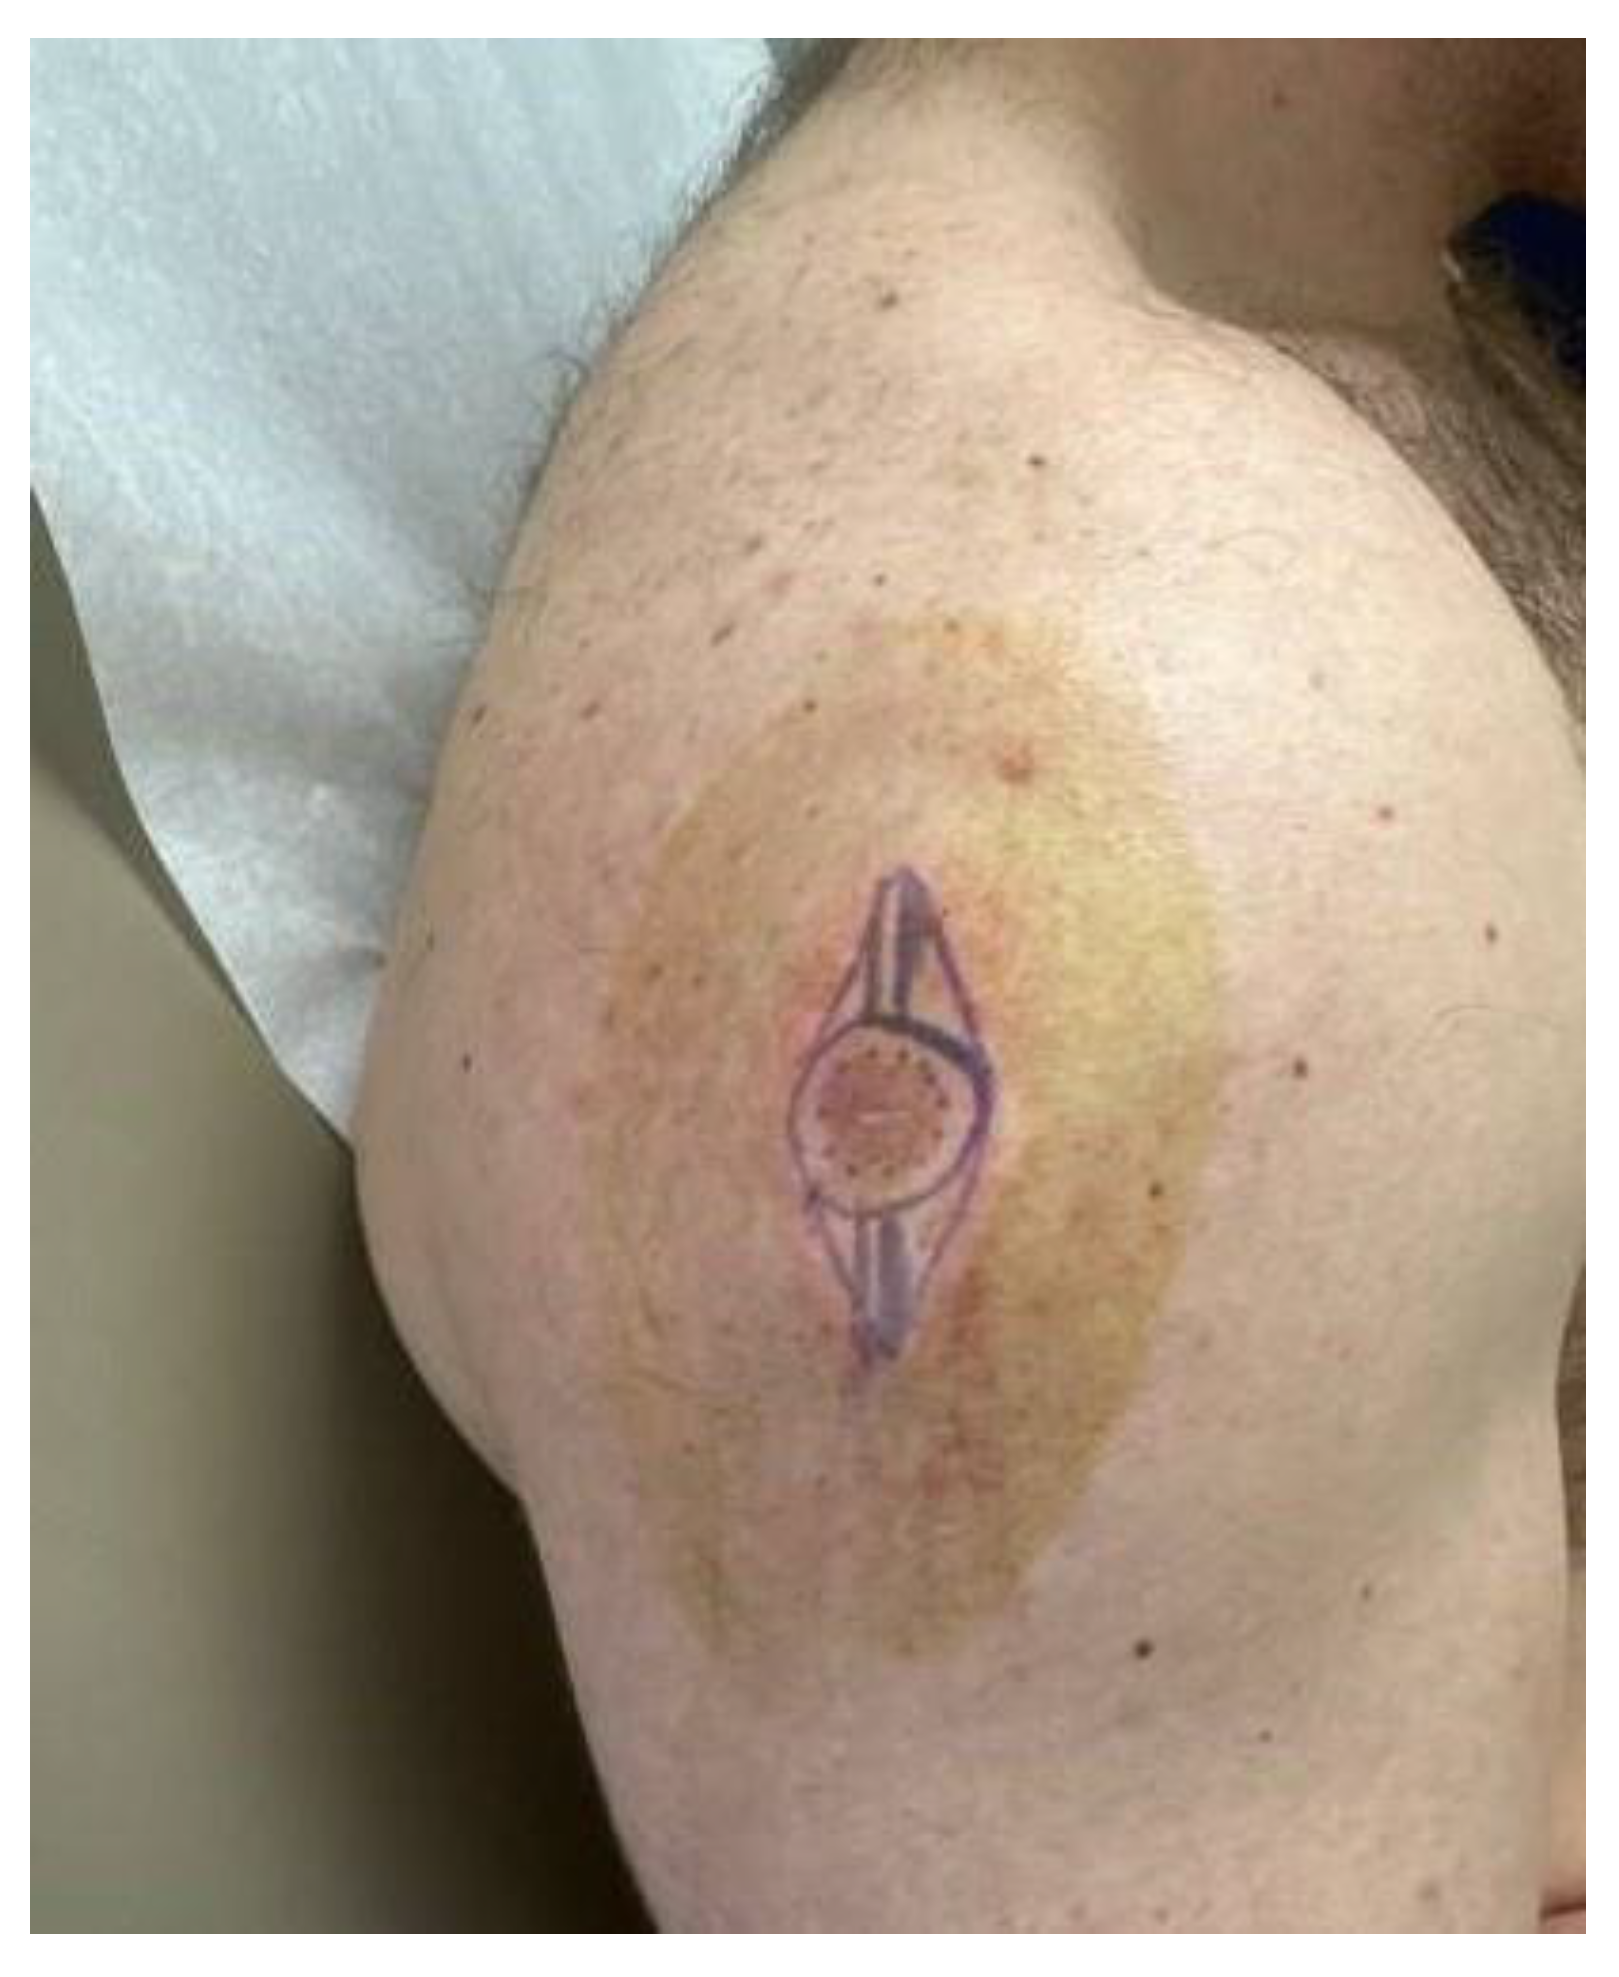

A 26-year-old male with a history of 0.4 mm malignant melanoma of the left upper extremity status post wide local excision and tenuous sun protection presented to clinic for follow-up. Exam revealed multiple scattered nevi to the head, trunk, extremities, feet, and genitalia as well as an erythematous plaque with central hyperpigmentation to the right upper arm in proximity to the shoulder (

Figure 1). A punch biopsy was obtained and revealed atypical myxoid spindle cell neoplasm and involved margins with overlying mildly atypical compound melanocytic nevus. The specimen also displayed CD34 positivity (histopathology displayed in

This case highlights an atypical presentation of spindle cell lipoma. The patient was a 26-year-old male with a history of malignant melanoma, who presented with an erythematous plaque on the right upper arm near the shoulder, an area that is not typically associated with SCL. Furthermore, the clinical presentation included central hyperpigmentation, which is not a common feature of SCL. The initial differential diagnosis was broad due to the atypical appearance of the lesion and CD34 positivity.